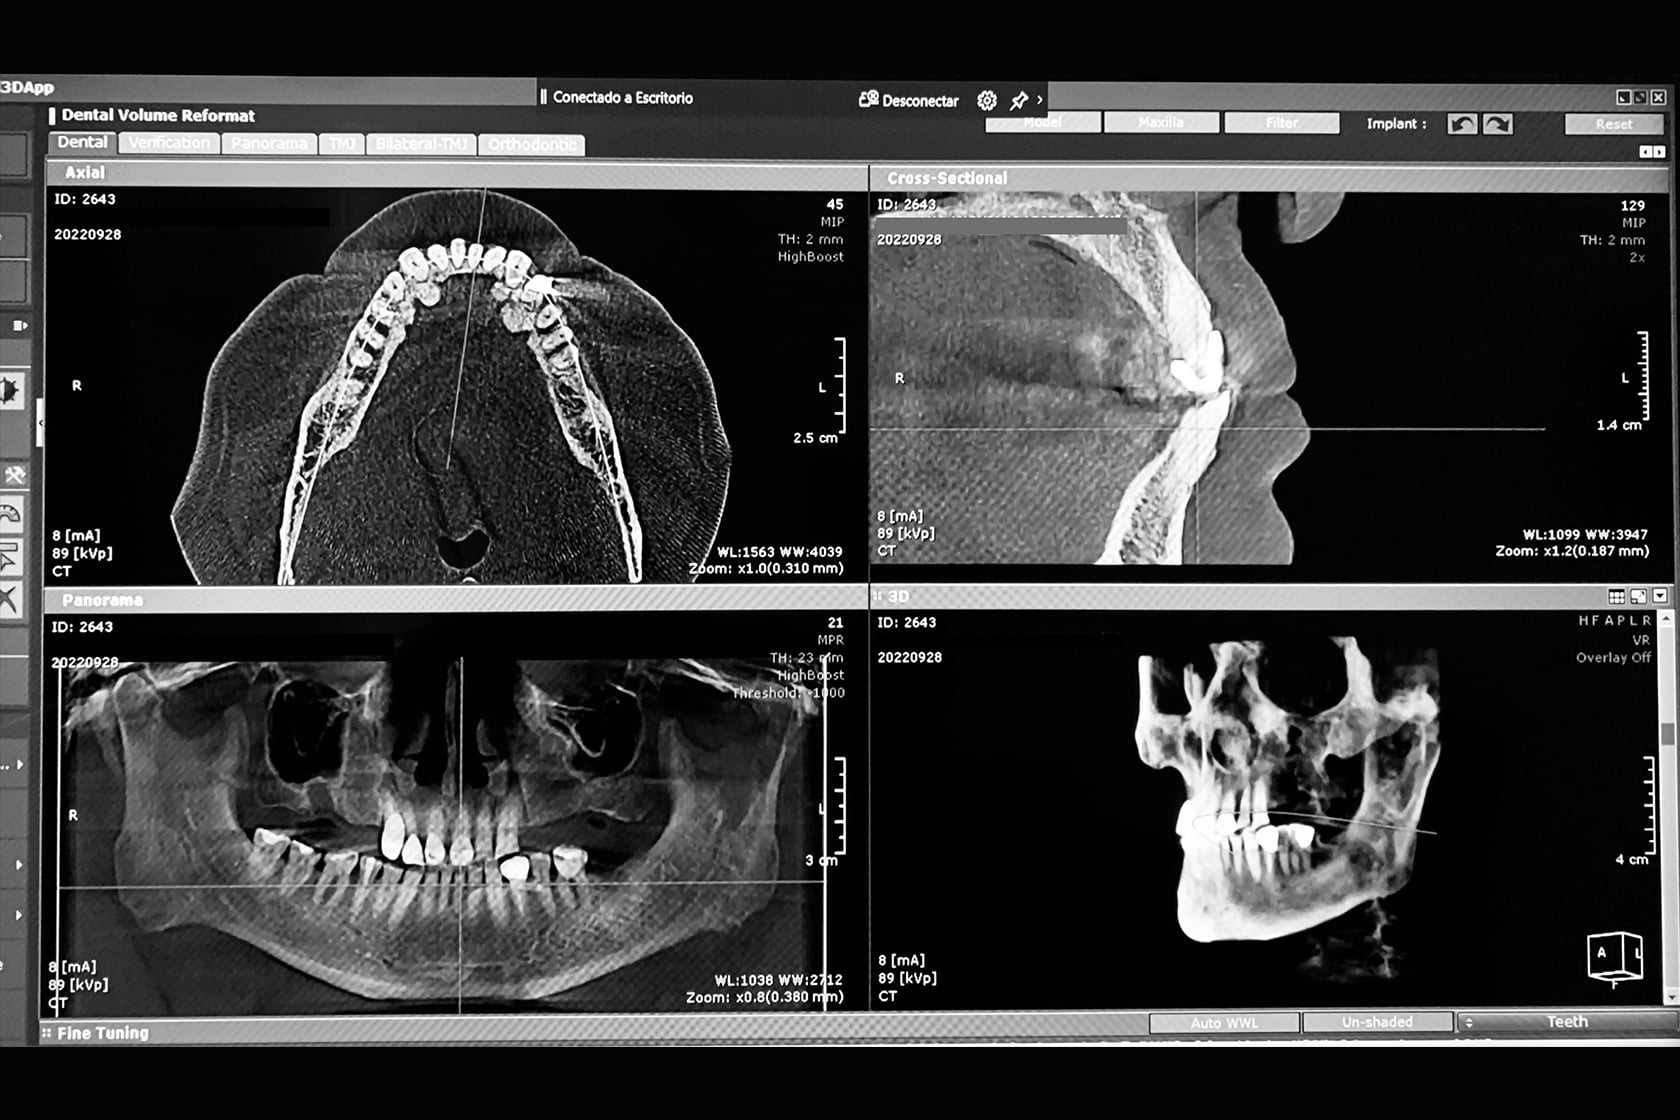

Radiología y Tomografías Digitales

Contamos con todos los conocimientos de las herramientas esenciales para el análisis e interpretación de las condiciones dentales de cada paciente.

Antes de cualquier trabajo, realizamos una completa evaluación de todas las estructuras óseas y dentales, para determinar el mejor plan de tratamiento. Con tecnología digital de última generación, nuestro equipo de profesionales está altamente capacitado para brindar una evaluación precisa y eficiente que permita garantizar resultados.